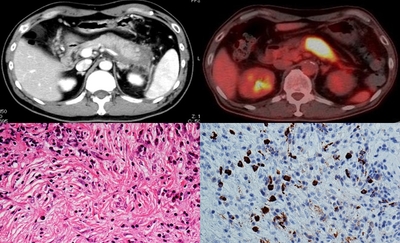

研究グループは、腸管バリア機能が低下する高齢男性に自己免疫性膵炎が多いことを踏まえ、腸管バリア機能を人工的に破綻させたマウスに自己免疫性膵炎を誘導し、腸管バリアと自己免疫性膵炎の関係を調べました。その結果、腸管バリアの機能低下によって、ブドウ球菌の一種であるシウリ菌が膵臓へ移行し、重度の自己免疫性膵炎を引き起こすことを明らかにしました。また、自己免疫性膵炎の病原性細菌がシウリ菌であることを世界で初めて突き止めました。

研究グループは、腸管バリアの破綻、腸内細菌バランスの乱れと自己免疫性の関係について調査しました。MRL/MpJマウスという自己免疫疾患モデルのマウスを用いて、ウイルスのRNAに類似した分子であるpoly(I:C)を注射し、自己免疫性膵炎を誘導しました。同時に高分子デキストランを飲水させることで、腸管バリア機能を障害しました。その結果、腸管バリアの破綻が自己免疫性膵炎を悪化させることを明らかにしました。この激しい膵炎を起こしたマウスでは、膵臓と大腸にIFN-αとIL-33を産生する形質細胞様樹状細胞が増加しており、膵臓と腸管で異常な免疫反応が共有されていました。

また、どのような菌が膵炎の悪化に関わっているのかを調べるために次世代シークエンス解析※7 を行ったところ、腸管バリアの破綻により激しい膵炎を起こしたマウスの便と膵臓からシウリ菌が検出されました。すなわち、腸内にいたシウリ菌が腸管バリアの破綻によって膵臓に移行し、膵炎悪化を起こしたと考えられます。

次に、無菌マウスとシウリ菌のみを定着させたマウスを用い、膵炎の悪化にシウリ菌が果たす役割を調査しました。無菌マウスでは少量のPoly(I:C)投与では軽度の膵炎しか起こりませんでしたが、シウリ菌のみしか存在しないマウスでは、通常では軽度の膵炎しか生じない少量のpoly(I:C)投与でも重度の膵炎を発症しました。このマウスでは、膵臓にIFN-αとIL-33を産生する形質細胞様樹状細胞を数多く認めました。このことから、シウリ菌が自己免疫性膵炎を悪化させる細菌であることが強く示唆されました。実際に、重度の膵炎を発症したマウスの膵臓から形質細胞様樹状細胞を分離して、ビフィズス菌、シウリ菌、クレブシエラ菌で刺激したところ、シウリ菌が効率よくIFN-αとIL-33の産生を誘導しました。